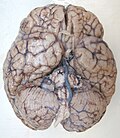

Brain: Lateral view

- Basal ganglia

- Includes: Nucleus caudatus, putamen, pallidum, subthalamus, substantia nigra

- Part of the forebrain.

- Caudate nucleus + putamen = striatum.

- Pallidum + putamen = lenticular nucleus.

Schematic overview (WC/blausen staff)

- Basal ganglia 1.jpg

Section with descriptions (WC/SMH)

- Uncus (as in uncal herniation).